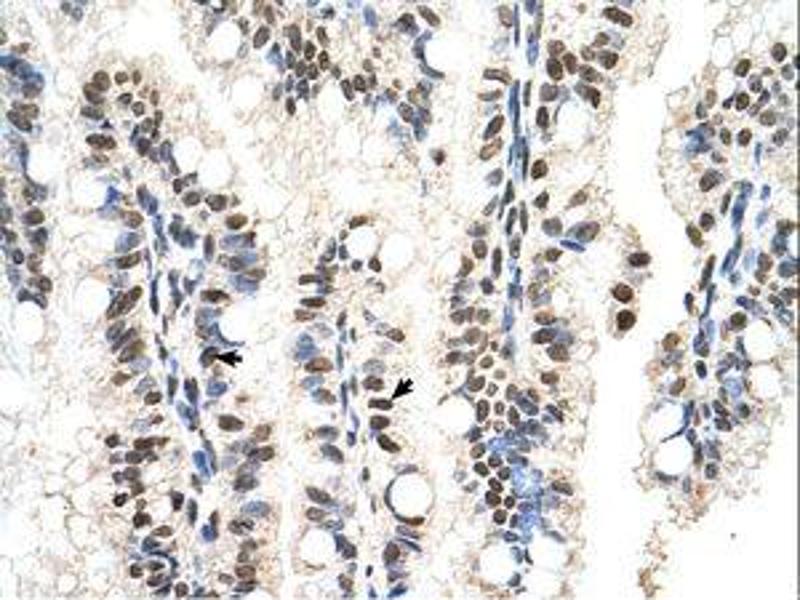

Western Blotting (WB), Immunohistochemistry (IHC), Immunohistochemistry (Paraffin-embedded Sections) (IHC (p))

Approved: IHC, IHC-P, WB